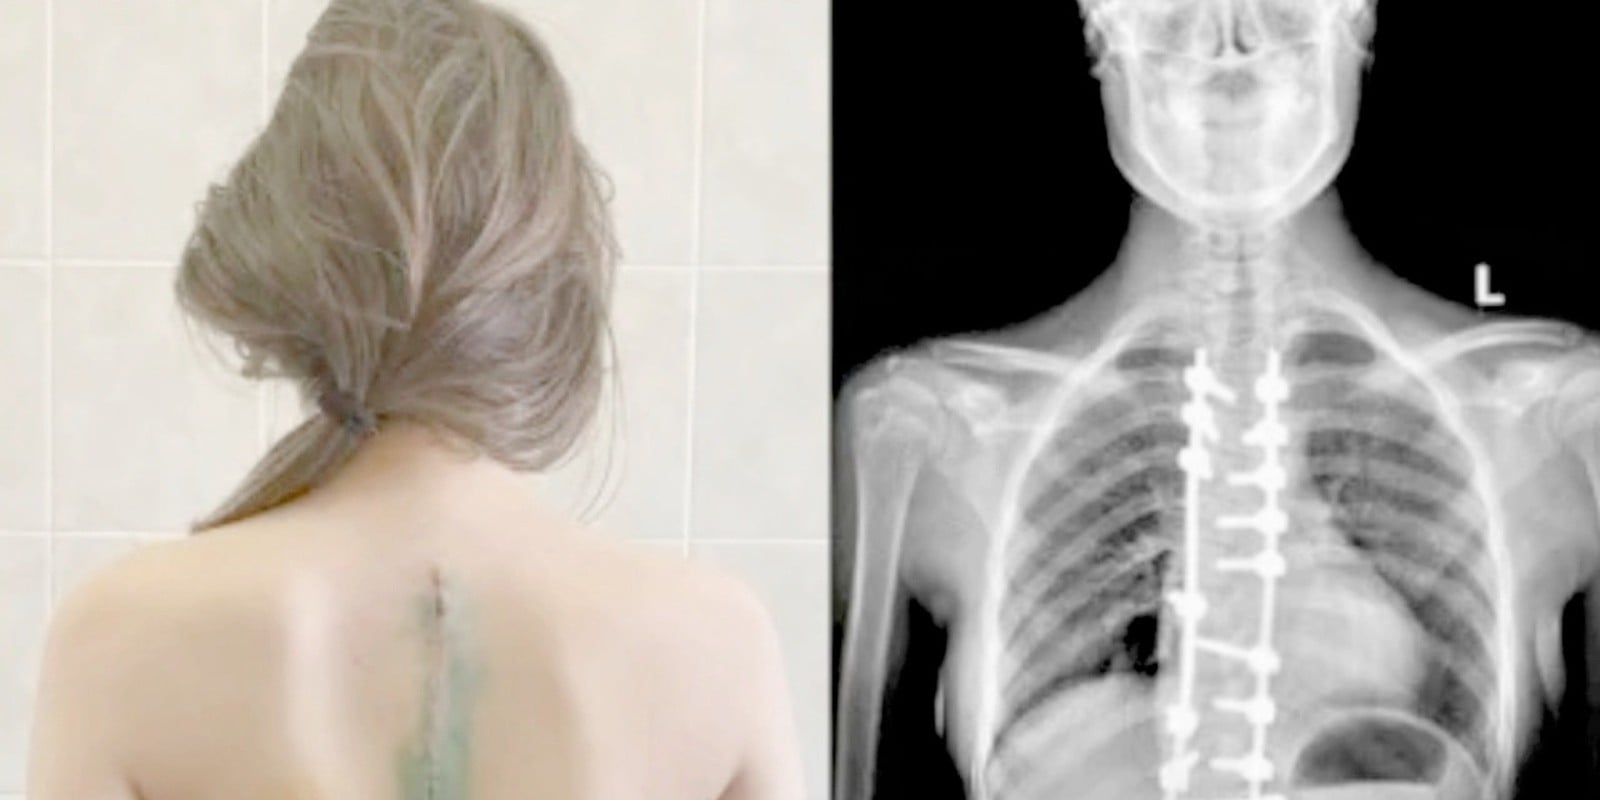

Он повесил снимок на экран. Позвоночник моей дочери. И вдоль него — россыпь белых точек. Много. Как будто кто-то рассыпал бисер внутри маленького тела.

— У вашей дочери нейробластома. Четвёртая стадия. Метастазы в костную ткань позвоночника, рёбер и, вероятно, таза. Нам нужна срочная биопсия и полное обследование, но по снимку… Денис, это запущено. Сильно запущено.

Я сидел и смотрел на неё. Не мог вдохнуть. Как будто воздух стал твёрдым и не помещался в лёгкие. Она протянула снимок — чистый позвоночник, без единой белой точки, без единой горошины бисера — и мне пришлось схватиться за стол, потому что комната поехала вбок.